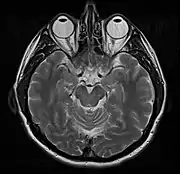

МРТ головного мозку

МРТ головного мозку застосовують у нейрохірургії і неврології, що дозволяє з високою точністю виявити патологію тканин головного мозку. Порівняно із КТ, цей метод забезпечує вищу чутливість під час діагностики невеликих пухлин та кращу візуалізацію задньої черепної ямки. Отримане зображення дає змогу виразно розрізнити сіру і білу речовину, що дозволяє діагностувати цілий ряд патологічних процесів у центральній нервовій системі, включаючи демієлінізуючі захворювання, деменцію, цереброваскулярні захворювання, нейроінфекції та епілепсію[9]. Оскільки під час дослідження отримують численні зображення із проміжком у кілька мілісекунд, це дозволяє побачити реакцію мозку на різні стимули, дослідити як функціональні, так і структурні аномалії мозку, та діагностувати більшість психічних розладів. Метод використовують також у стереотаксичній хірургії під контролем МРТ — в радіохірургії для лікування пухлин головного мозку, артеріовенозних мальформацій та інших захворювань, що потребують хірургічного лікування.